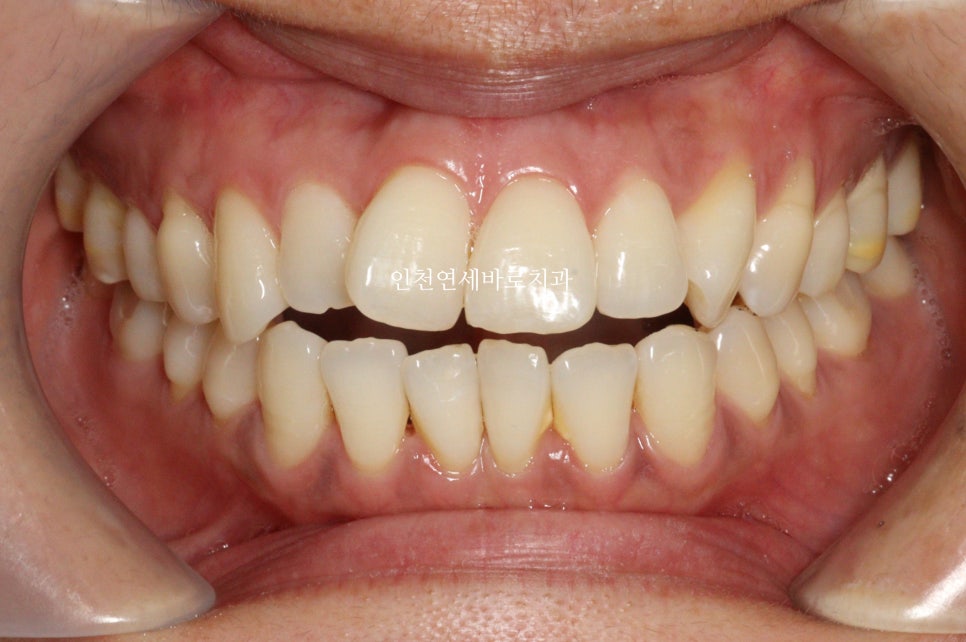

첫 세트 완료 시점

첫세트가 끝날때 이미 거의 다 완성이 된 상태였습니다

그래도 한번의 재제작이 가능한 상황에서 아까운 마음이 들어 재제작을 하기로 결정

조금 더 세세한 조절을 하기도 했습니다